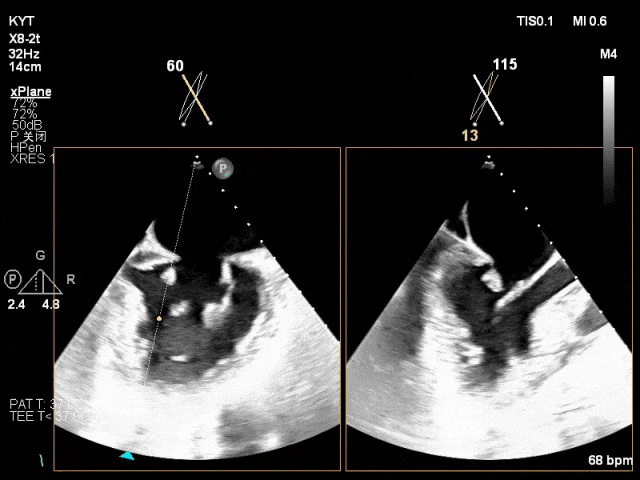

术前超声评估结果:

二尖瓣PC区收缩期脱向左房侧,其上可见飘带样回声。二尖瓣口左房侧见大量反流信号,主要呈偏心性并沿前叶走行达房顶并折返。

术前TTE及TEE影像:

TEE X-plane示二尖瓣内交界区脱垂